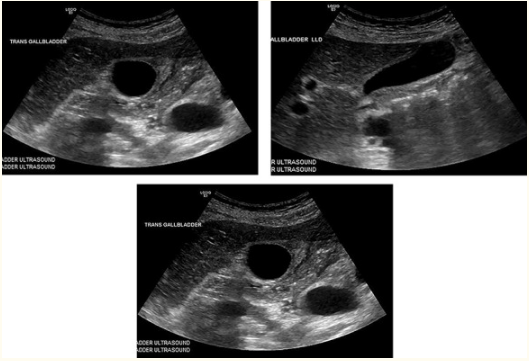

一名产后34岁女性患者,孕3产2,产后5天因右上腹疼痛于我院急诊就诊,尤其以餐后疼痛为主,伴有恶心呕吐,24小时内患者疼痛加重。查体发现患者生命体征平稳,上腹偏右侧区域压痛明显,伴有轻度腹胀,无腹膜炎体征,但患者墨菲征阳性。实验室检查回报,白细胞升高,钾低。肝胆脾彩超检查发现患者胆囊壁增厚,0.45cm,胆囊周围可见积液,未见胆结石,胆总管直径正常,如图1-3所示。

图1-3 胆囊壁增厚,0.45cm,胆囊周围可见积液,未见胆结石,胆总管直径正常